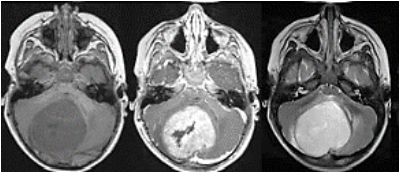

Encaminhado a um pronto socorro pediátrico aonde foi submetido a ressonância nuclear magnética (RNM – figura 3):

Figura 3 RNM de crânio